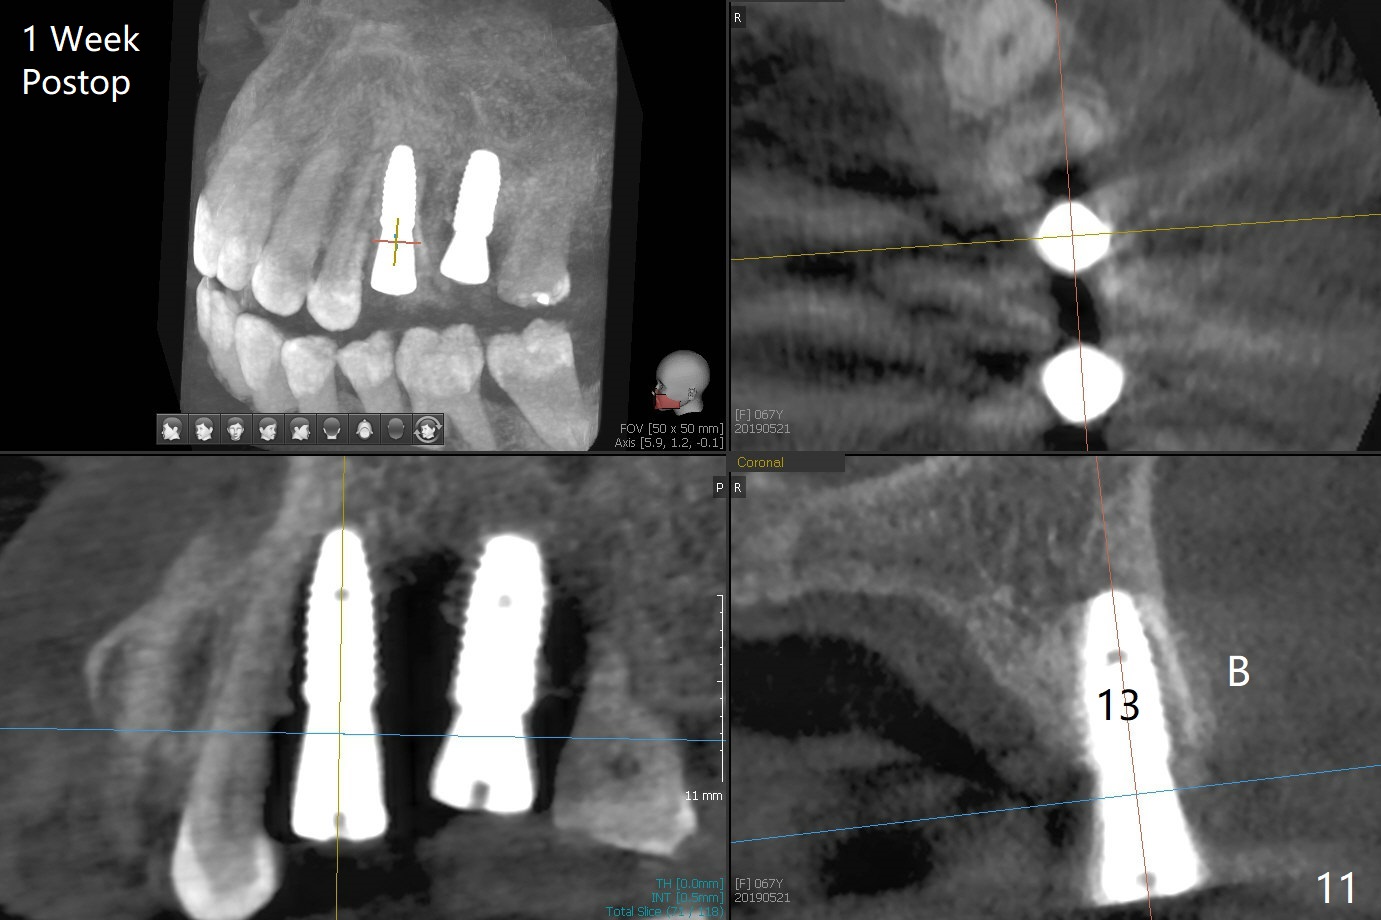

After extraction of the tooth #13 residual root, the bone in the distal wall of the socket looks white. Intraop PA rules out root structure (Fig.1 *). Osteotomy is conducted according to drill sequence. Bitewings are taken to check implant placement level (Fig.2,3). Following implant level adjustment and healing abutment installment (Fig.4,5 (*: bone graft)), the implant at #13 is found to be close the root of #12 (Fig.6 *), i.e., not parallel to the implant at #14. Introspectively, 2.2x10 mm drill seems to be long. When it touches the bone, the cylinder portion of the drill (Fig.7 red) does not engage into the sleeve (green). When it goes into the bone, it may have been deflected mesial due to the slope of the distal wall of the socket (hard bone, Fig.8 open arrow)). If a shorter drill (such as 2.2x7.3 or 8.5 mm) were used (Fig.9), the deflection would be minimal if drilling is slow (Fig.10). CT taken 1 week postop shows that the implant at #13 is approximately 1 mm near the root of the tooth #12, but the neurovascular bundle to the latter seems not to have been interrupted (Fig.11,12). The buccopalatal trajectory at #14 is within normal limit (Fig.11,13 (B: buccal)). There is no periapical radiolucency at #12 five months postop (Fig.14). However the cemented abutments are incompletely seated (<). The patient is reluctant to return for impression 17 months postop (due to coronavirus); with attention, the same abutment at #13 is reseated completely; an abutment with longer cuff and narrower diameter is also seated completely (Fig.15).